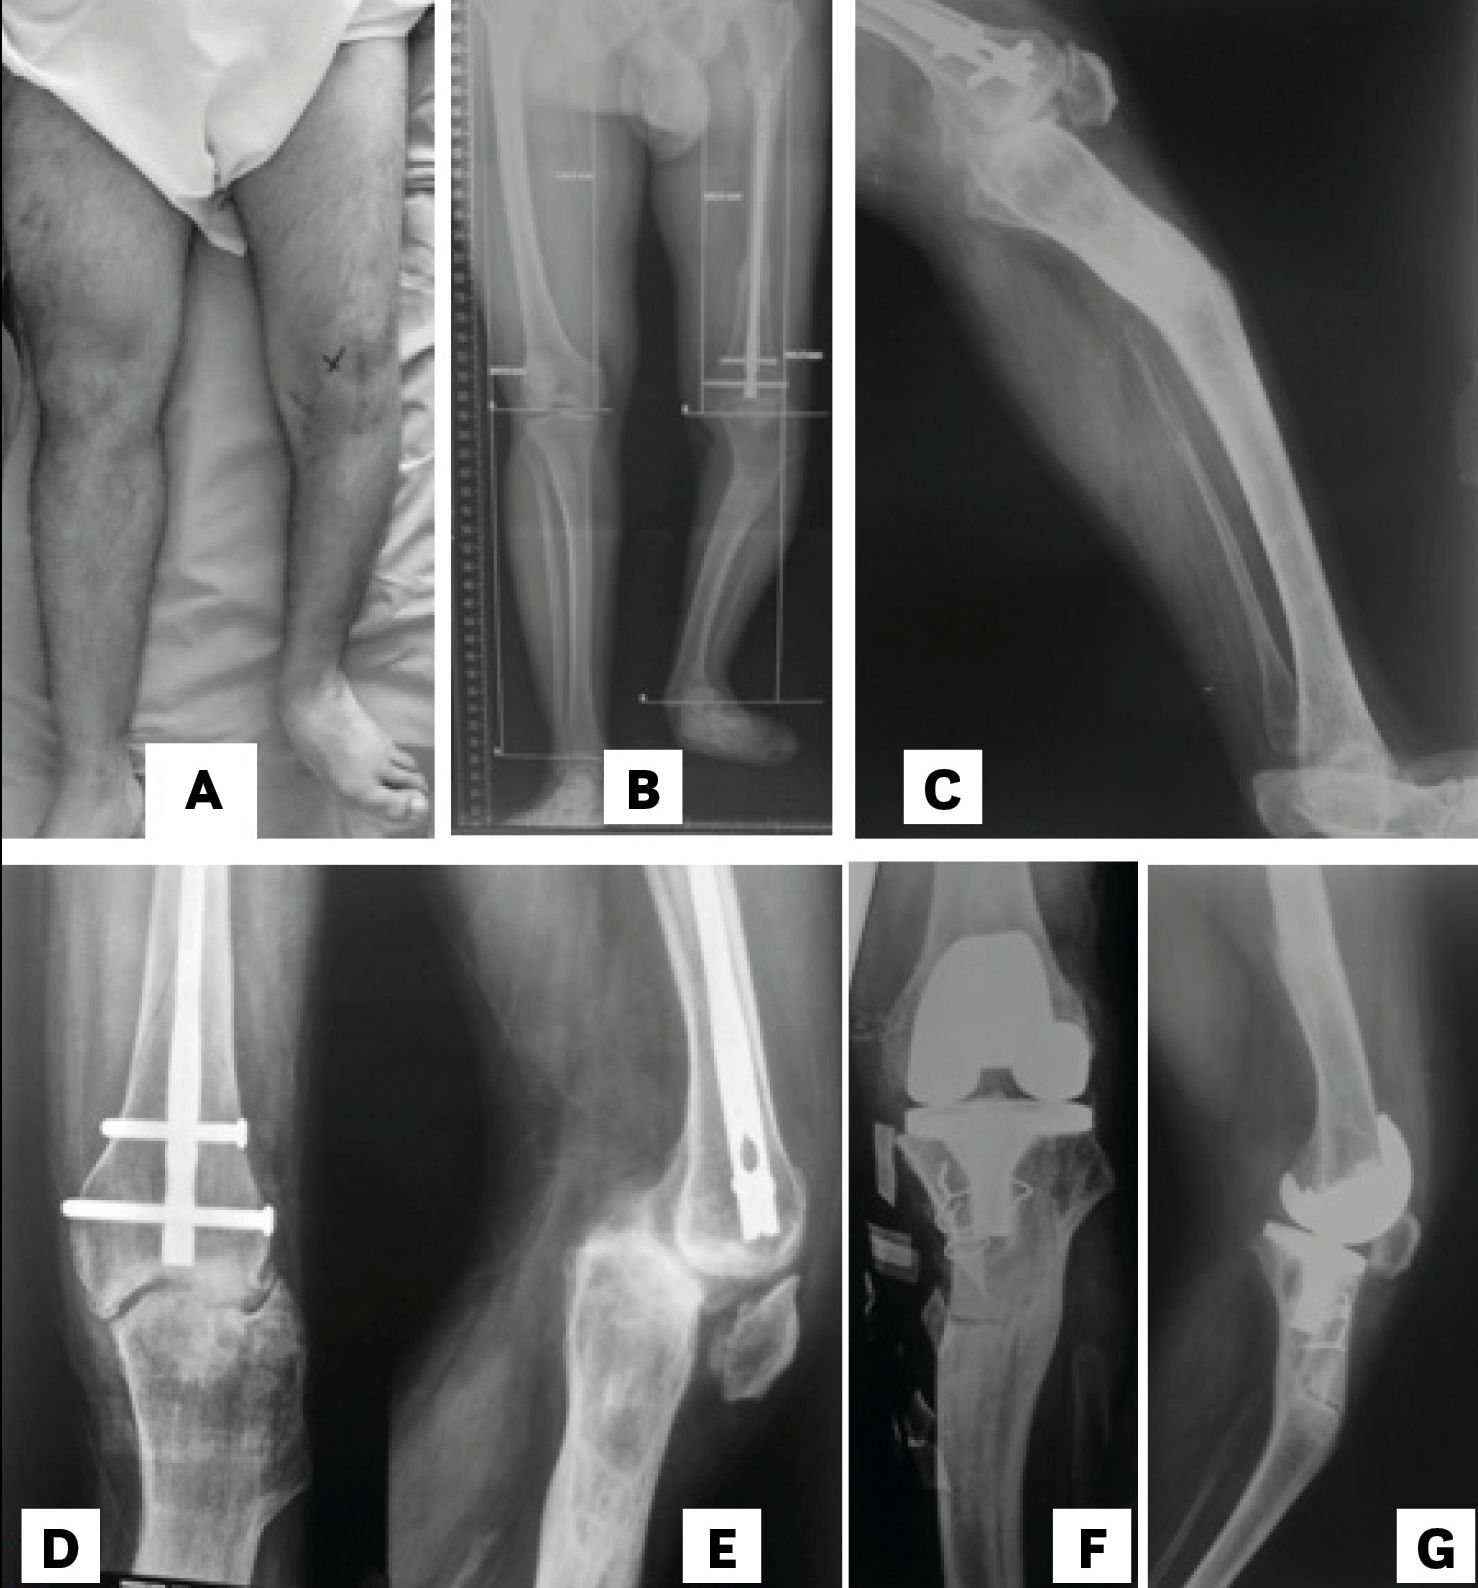

It is essential to know the aetiology of the deformity and its location regarding the knee in order to evaluate its real influence on the mechanical axis of the limb. [1], Jeffery RS, Morris RW, Denham RA Coronal alignment after total knee replacement. JBJS Br 1991;73(5):709.[3], Panayiotis JP, Karachaloios T, Themistocleous GS Total knee arthroplasty in patients with pre-existing fracture deformity. Orthopedics. 2007;30(5):373.[4] Wolff AM, Hungerford DS, Pepe CL The effect of extraarticular varus and valgus deformity on total knee arthroplasty. Clin Orthop. 1991;271:35-51. The nearer to the joint the deformity is, the more it will affect the mechanical axis and the intraarticular bone correction cuts (1/3 third rule – Figure 4).

The distal femoral bone cut can be planned using as reference the femoral mechanical axis (cut in 90°) or preferably the axis of the femur proximal to the deformity. The correction of the extra-articular deformity can be made through intra-articular cuts when the femoral distal cut line respects the MCL insertion, since on the lateral side, a lateral epicondylar osteotomy can be performed similar as when dealing with severe valgus deformities. (Figure 5 A & B). [2], Mullaji Arun, Shetty GM Computer-Assisted Total Knee Arthroplasty for arthritis with extra-articular deformity. J. Arthroplasty. 2009;24(8):1164.[3], Panayiotis JP, Karachaloios T, Themistocleous GS Total knee arthroplasty in patients with pre-existing fracture deformity. Orthopedics. 2007;30(5):373.[4], Wolff AM, Hungerford DS, Pepe CL The effect of extraarticular varus and valgus deformity on total knee arthroplasty. Clin Orthop. 1991;271:35-51.[6],Wang JW, Wang CJ Total knee arthroplasty for arthritis of the knee with extra-articular deformity. JBJS Am. 2002;84(10):1769-1774.[8], Mann JW, Insall JN, Scuderi GR Total knee arthroplasty in patients with associated extra-articular angular deformity. Orthop Trans. 1997;21:59.[15] Rand JA, Franco MG Revision considerations for fractures about the knee. In: Goldberg VM (Ed.), Controversies of total knee arthroplasty. Raven Press Ltd, New York, USA, pp. 1991;235-247.

The proximal tibial bone resection must be made at 90° to the axis of the tibial shaft distal to the deformity (Figure 5 C & D).[8], Mann JW, Insall JN, Scuderi GR Total knee arthroplasty in patients with associated extra-articular angular deformity. Orthop Trans. 1997;21:59.[2], Mullaji Arun, Shetty GM Computer-Assisted Total Knee Arthroplasty for arthritis with extra-articular deformity. J. Arthroplasty. 2009;24(8):1164.[3], Panayiotis JP, Karachaloios T, Themistocleous GS Total knee arthroplasty in patients with pre-existing fracture deformity. Orthopedics. 2007;30(5):373.[15] Rand JA, Franco MG Revision considerations for fractures about the knee. In: Goldberg VM (Ed.), Controversies of total knee arthroplasty. Raven Press Ltd, New York, USA, pp. 1991;235-247. The use of guides is ruled by the same principles as for the femur.[6]Wang JW, Wang CJ Total knee arthroplasty for arthritis of the knee with extra-articular deformity. JBJS Am. 2002;84(10):1769-1774. A difference is that an “unusual” cut of the tibia generates an asymmetrical gap for the extension and flexion gap equal, which makes these deformities easier to correct through a proper soft tissue release. Nevertheless, there is controversy about the severity of the deformity in which the correction must be performed with an extra-articular osteotomy. [2], Mullaji Arun, Shetty GM Computer-Assisted Total Knee Arthroplasty for arthritis with extra-articular deformity. J. Arthroplasty. 2009;24(8):1164.[3], Panayiotis JP, Karachaloios T, Themistocleous GS Total knee arthroplasty in patients with pre-existing fracture deformity. Orthopedics. 2007;30(5):373.[4], Wolff AM, Hungerford DS, Pepe CL The effect of extraarticular varus and valgus deformity on total knee arthroplasty. Clin Orthop. 1991;271:35-51.[10], Radke S, Radke J Total knee arthroplasty in combination with a one-stage tibial osteotomy. Journal of Arthroplasty. 2002;17(5):533.[11], Windsor RE, Insall JN, Vince KG Technical considerations of total knee arthroplasty after proximal tibial osteotomy. JBJS Am. 1988;70(4):547.[16] Ritter MA, Faris GW Total knee replacement following extra-articular deformities. Orthopedics 2003;26:969.In patients with multiplanar or complex deformities, this possibility is more evident. In case of extra-articular osteotomy combined with TKA in a single stage procedure, the method used to stabilize the osteotomy must be defined. We prefer, if possible, to use femoral or tibial stems instead of plates and screws.